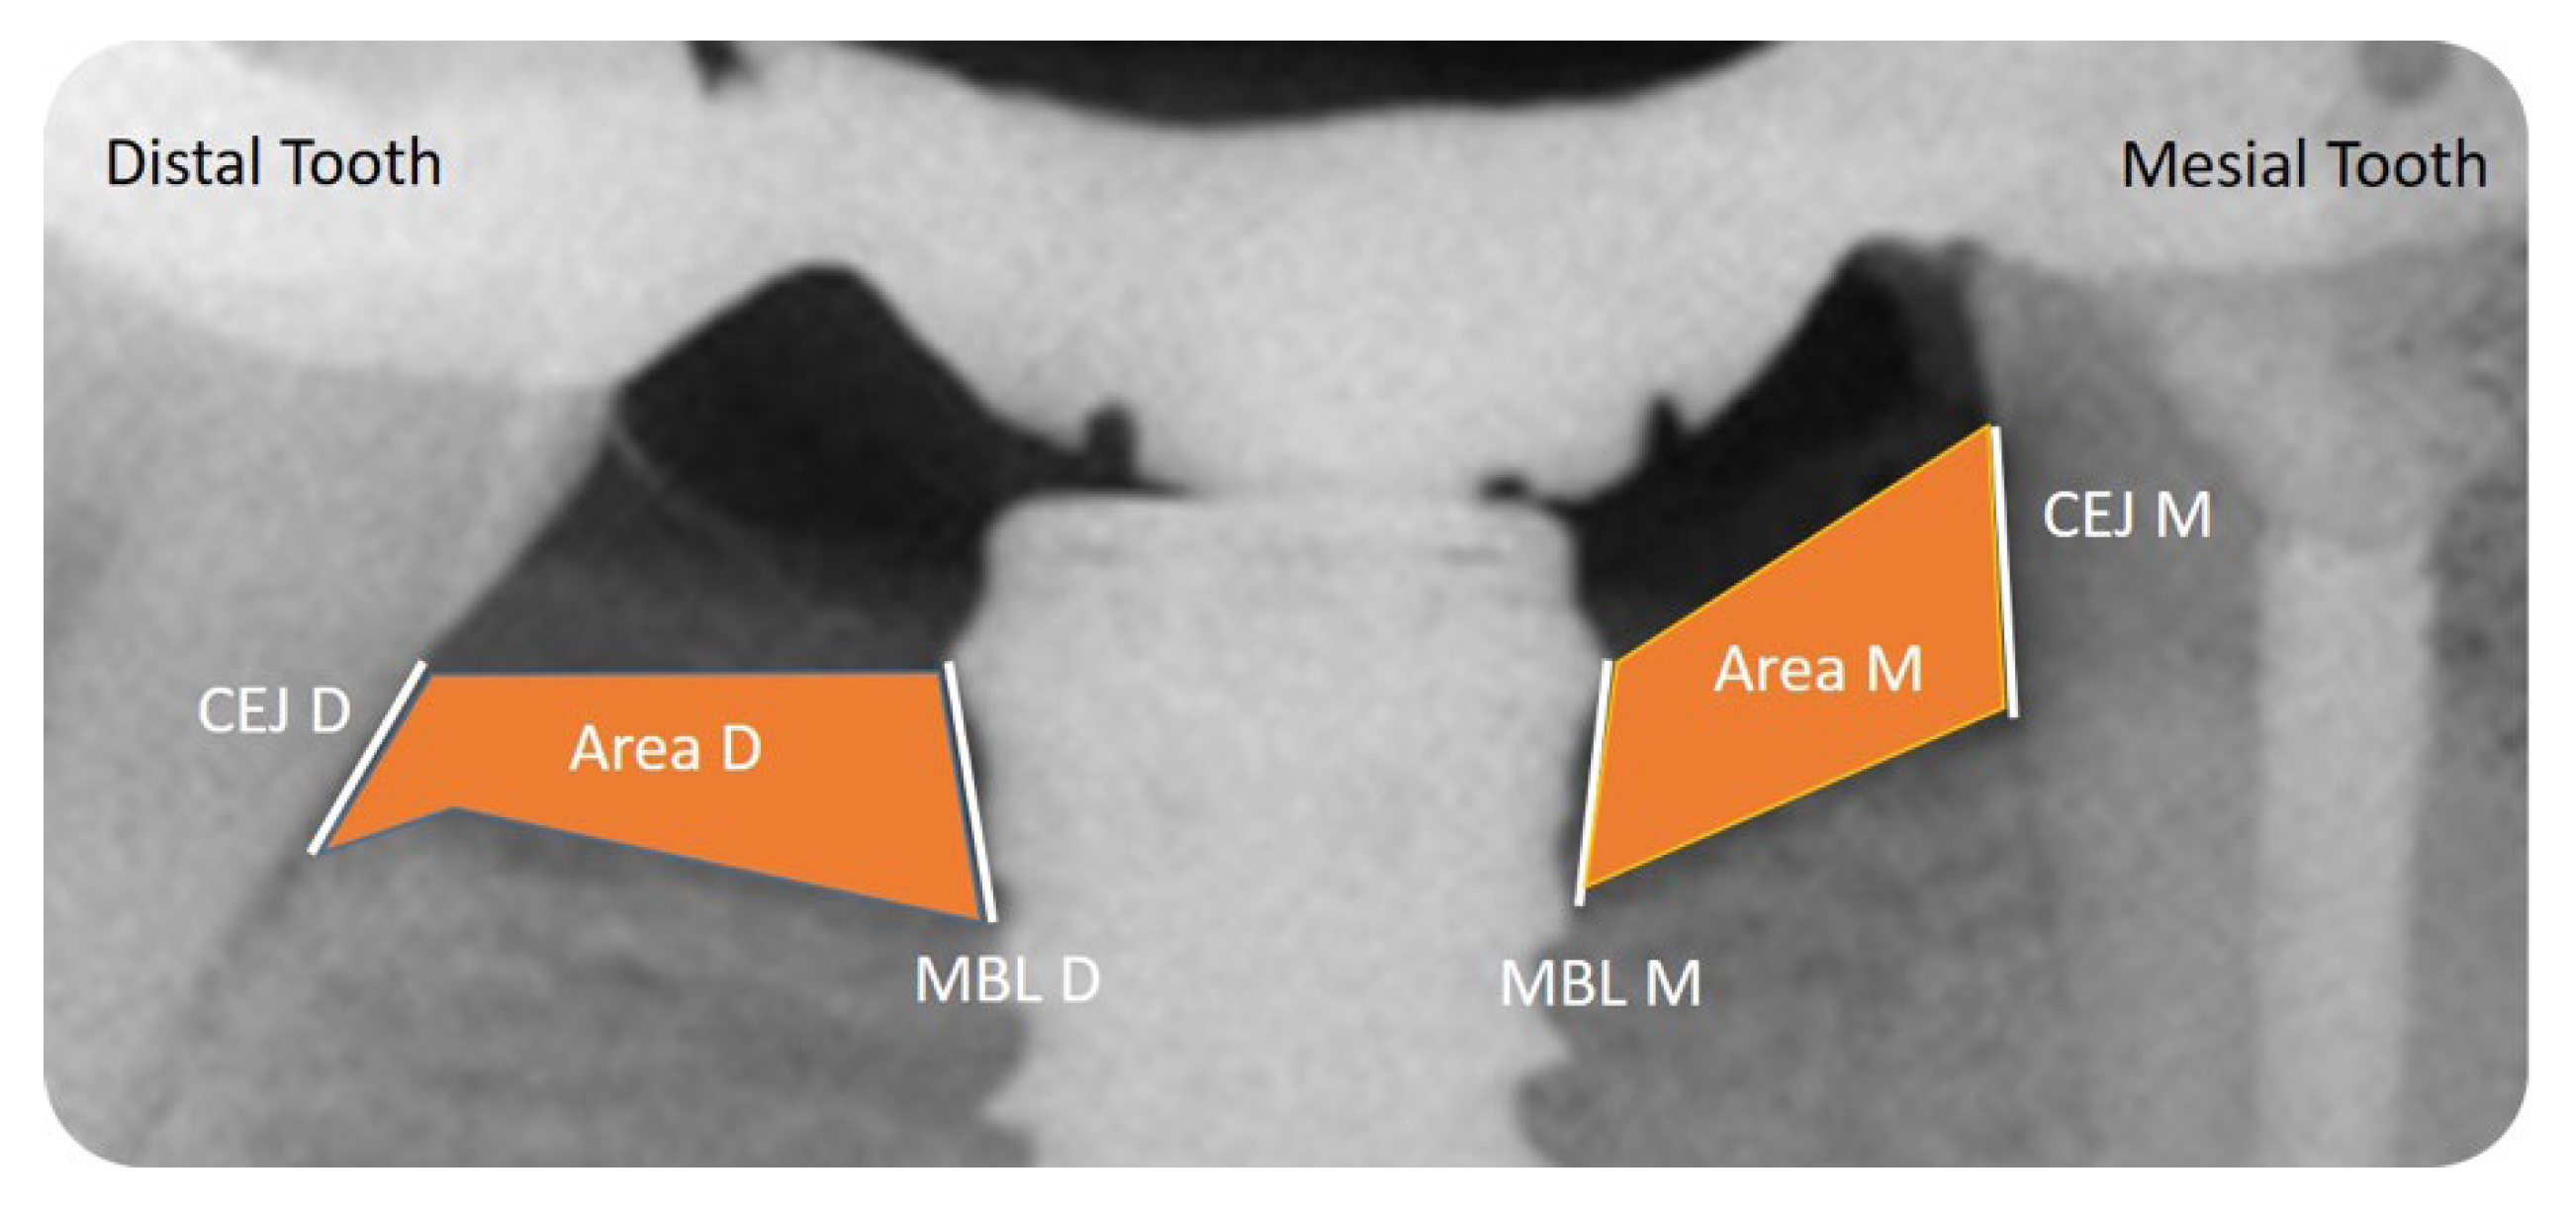

2.9. Radiographic Evaluation

- -

- Mesial and Distal Marginal Bone Levels (MBL-M and MBL-D)

- Mesial and Distal Cement–Enamel Junction (CEJ-M and CEJ-D)

- Mesial and Distal Bone Level Area (Area-M and Area-D)